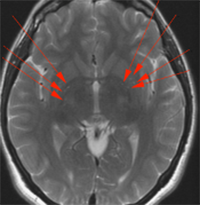

FIG 2. Diffuse ischemic lesions of the deep white matter. MRI of a patient with Filum Disease showing numerous focal ischemic lesions in the hemispheric deep white matter, the basal ganglia (red arrows), which disappeared after surgery.

Our medical and research team described a new condition, the Filum Disease, in which a diffuse alteration in the cerebral blood circulation was observed, predominantly in the white matter areas (Figure 2) 3.

We can assume that the predisposition to other brain injuries due to endothelitis can aggravate or increase sequelae in patients with COVID-19 and Filum Disease.